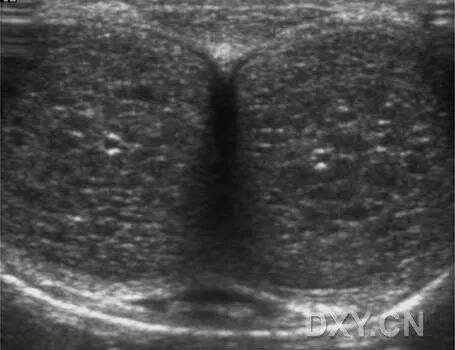

正常的灰阶超声解剖。轴向扫描。A 松软状态下阴茎表现为中等回声的均质结构。

在松软状态下,阴茎海绵体在超声上表现为圆柱样的中等均质回声。尿道海绵体和阴茎头要比阴茎海绵体的回声高。尿道在塌陷状态下表现为横线样。